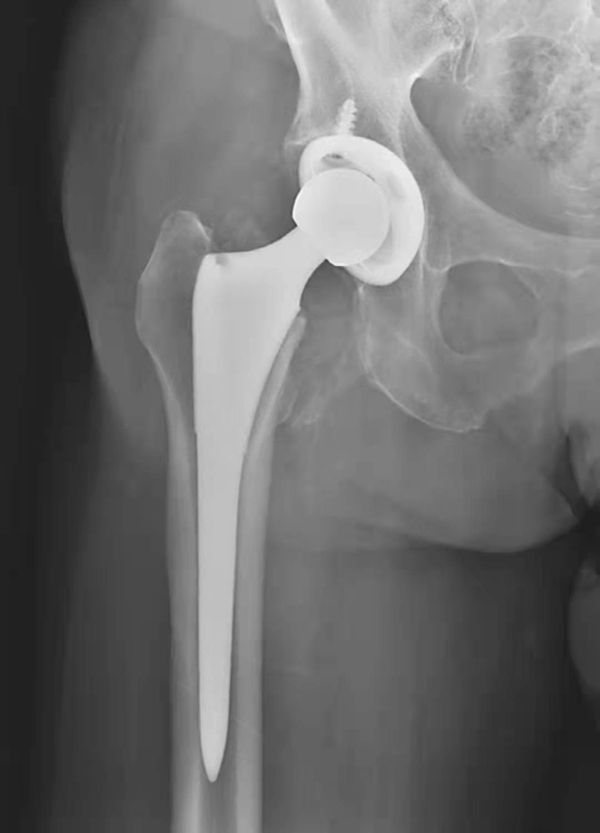

图3 无菌性松动

平片,示右侧髋臼杯周围骨质吸收,髋臼杯松动并向上内侧移位